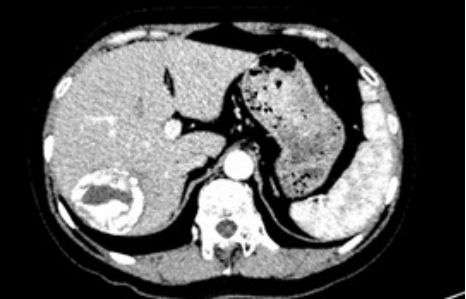

潘阿姨(化名)怀揣着忐忑的心来到了哈医大一院,在此之前,阿姨因体检发现肝占位,辗转多家医院,但都无法得到明确的诊断。患者既往10年前曾有过牛羊养殖史,病灶巨大且位置刁钻,通过增强CT发现患者病灶大小约6.0×4.7cm,位于Ⅵ、Ⅶ段,毗邻着门静脉右支,手术难度大,风险高。为此,阿姨深受困扰,直到她慕名来到哈医大一院门诊找到姜洪池教授团队。

入院后,通过AFP、PIVKA-II及彩超的影像学检查,排除了恶性病变的可能,最终诊断为肝包虫病。考虑到肿物为肝脏良性病变,且保留肝脏功能对患者至关重要,姜洪池教授团队决定采用腹腔镜方式,暨通常所讲的“微创方式”进行治疗。经过术前一系列准备,在姜洪池教授、金也医生、刘嘉铭医生,以及手术室贺轶宁护士、国鹏护士熟练配合下,紧贴病灶边缘,最大限度地保留了病灶附近的血管、肝蒂、正常肝组织,完整地切除了包虫病灶,成功保证了患者术后的肝功能状态。手术历时3个小时余,出血仅30ml,术后患者安返病房,目前患者已康复归家。